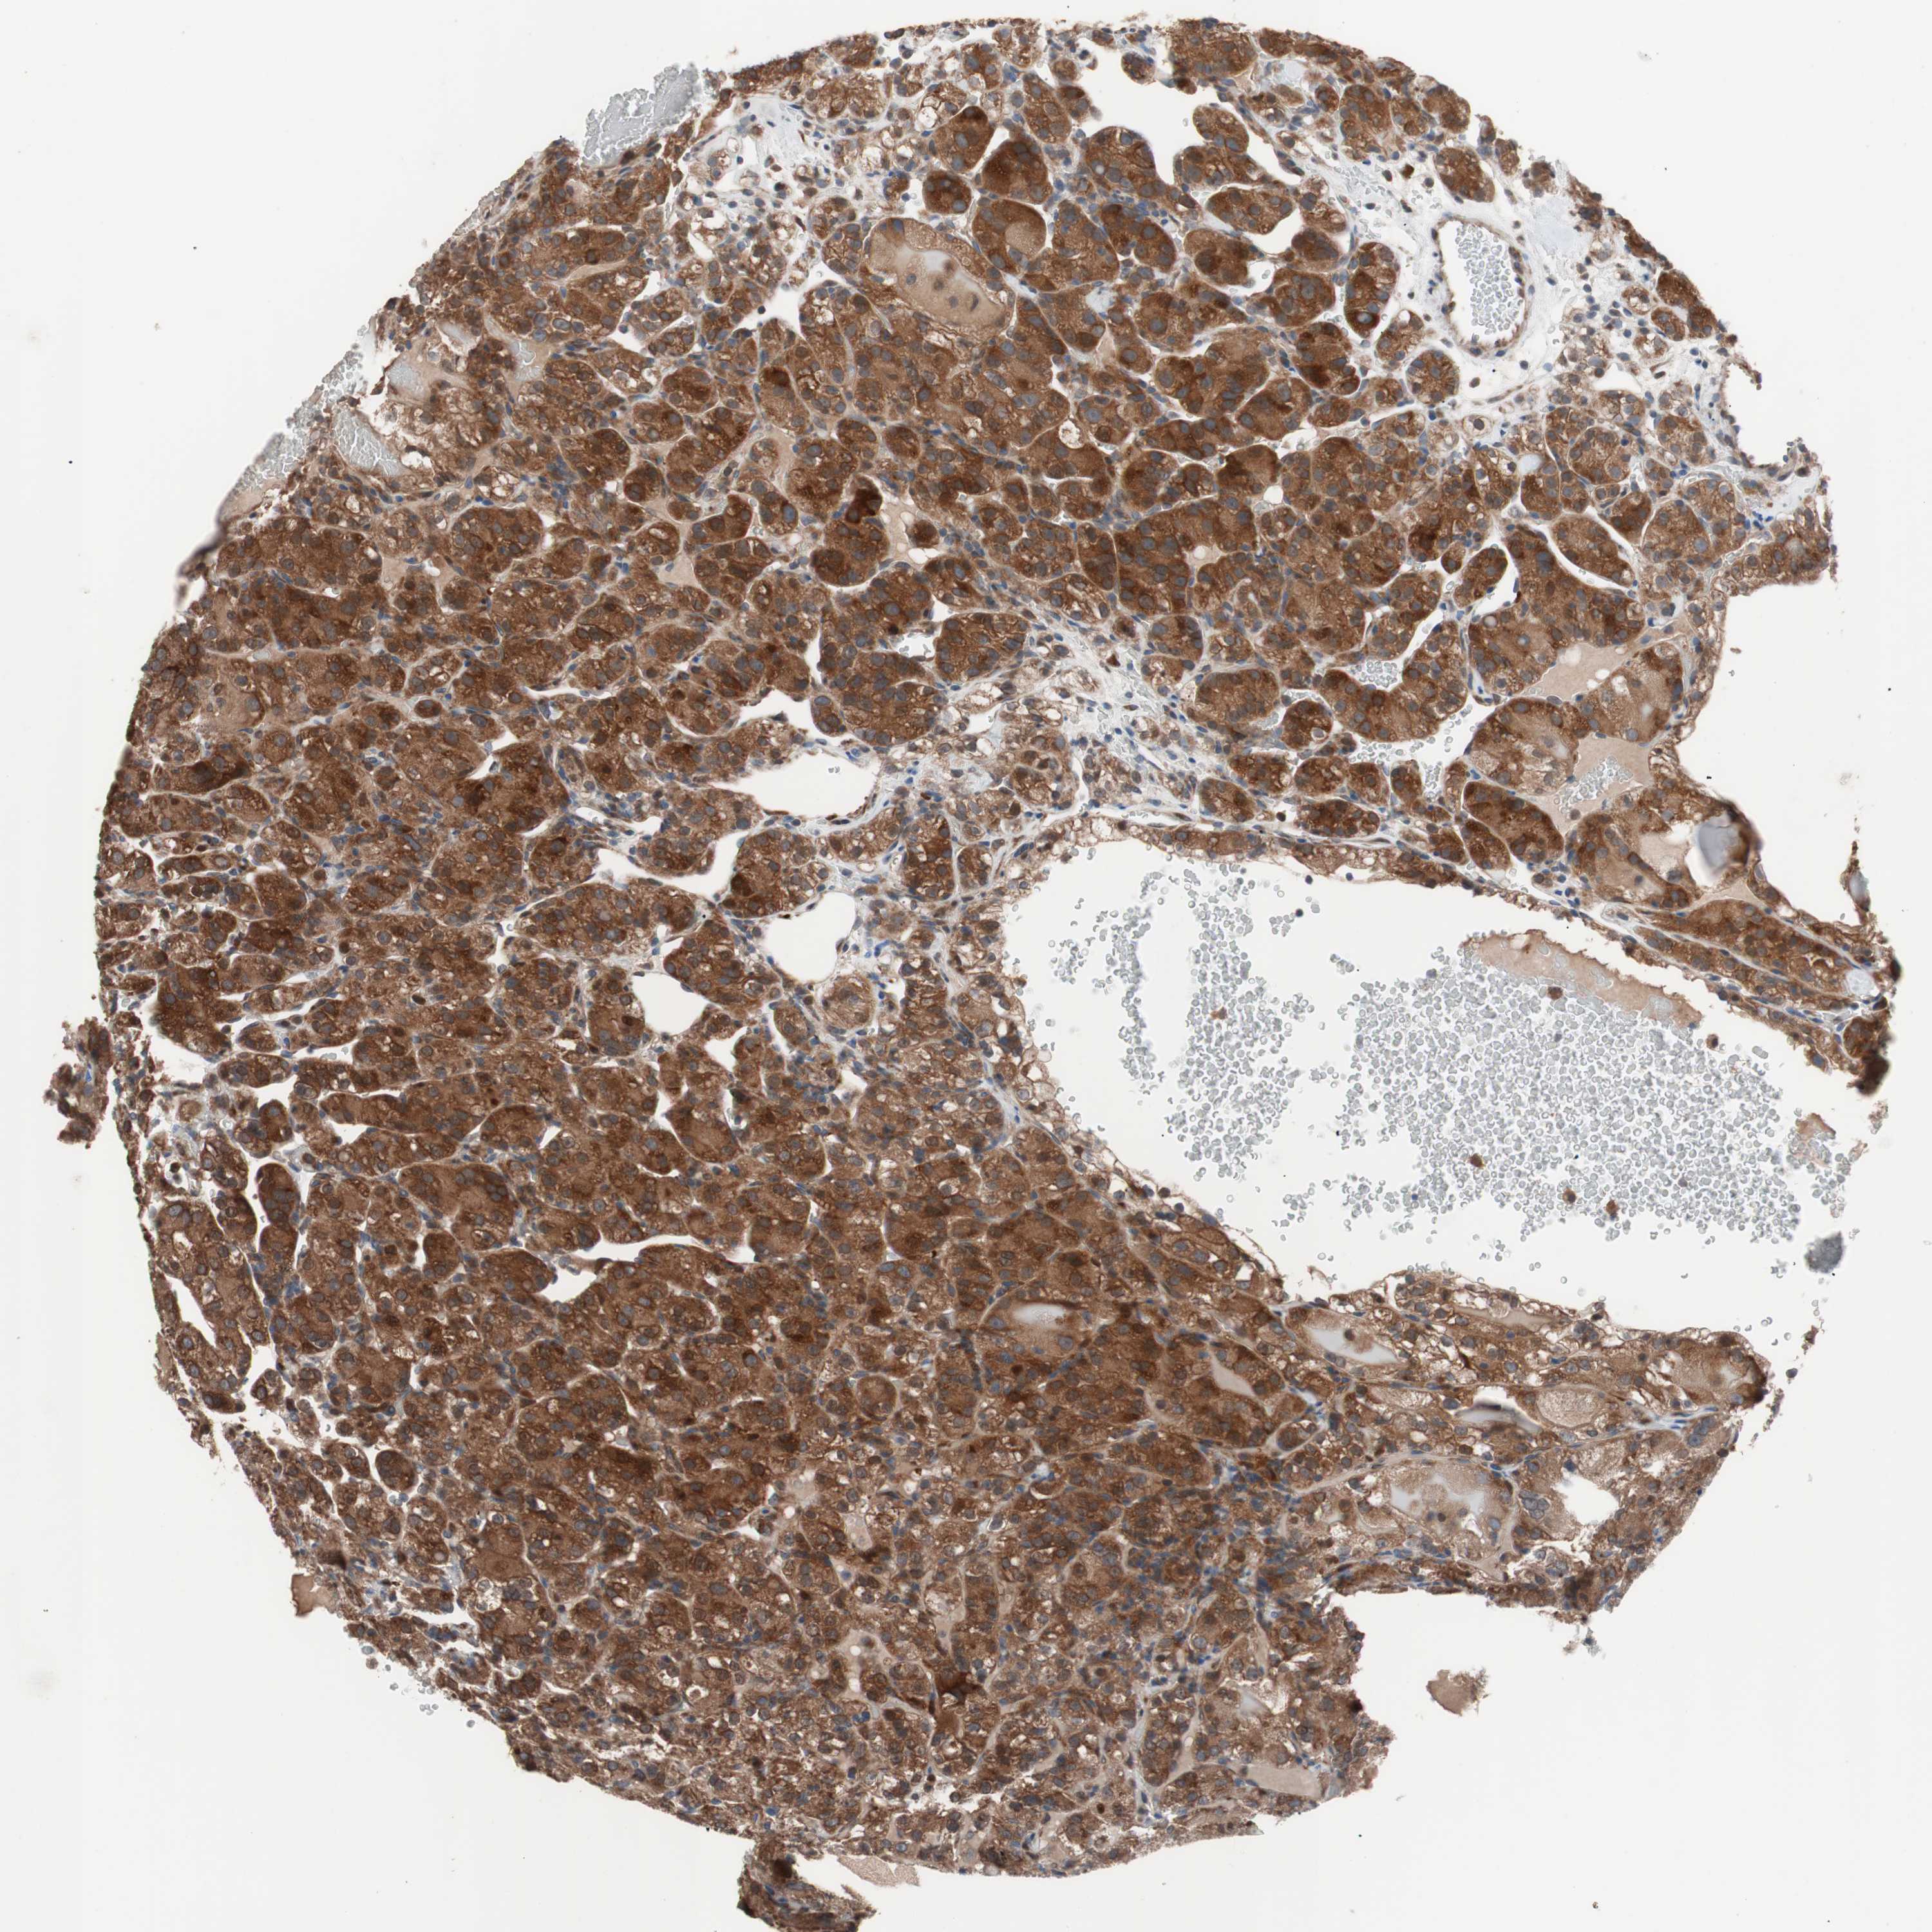

KIDNEY RENAL CLEAR CELL CARCINOMA (VALIDATION) - Interactive survival scatter ploti

The Survival Scatter plot shows the clinical status (i.e. dead or alive) for all individuals in the patient cohort, based on the same data that underlies the corresponding Kaplan-Meier plots. Patients that are alive at last time for follow-up are shown in blue and patients who have died during the study are shown in red.

The x-axis shows the expression levels (FPKM) of the investigated gene in the tumor tissue at the time of diagnosis. The y-axis shows the follow-up time after diagnosis (years). Both axes are complimented with kernel density curves demonstrating the data density over the axes. The top density plot shows the expression levels (FPKM) distribution among dead (red) and alive patients (blue). The right density plot shows the data density of the survived years of dead patients with high and low expression levels respectively, stratified using the cutoff indicated by the vertical dashed line through the Survival Scatter plot. This cutoff is automatically defined based on the FPKM cutoff that minimizes the p-score. The cutoff can be changed by dragging the vertical line or by entering a cutoff value in the square labeled "Current cut-off".

Under the Survival Scatter plot the p-score landscape (black curve; left axis) is shown together with dead median separation (red curve; right axis). Dead median separation is the difference in median mRNA expression between patients who have died with high and low expression, respectively. It is calculated as follows: median FPKM expression of dead patients with high expression - median FPKM expression of dead patients with low expression. This is intended to aid the user in visually exploring custom cutoffs and the associated p-scores and dead median separation.

Individual patient data is displayed and can be filtered by clicking on one or more of the category buttons on the top of the page. Categories describing expression level and patient information include: high, low, alive, dead, female, male and tumor stages. The scale of the x-axis can be toggled between linear and log-scale by clicking on the "x log" button. Mouse-over function shows TCGA ID, patient information and mRNA expression (FPKM) for each patient.

& Survival analysisi

Kaplan-Meier plots summarize results from analysis of correlation between mRNA expression level and patient survival. Patients were divided based on level of expression into one of the two groups "low" (under cut off) or "high" (over cut off). X-axis shows time for survival (years) and y-axis shows the probability of survival, where 1.0 corresponds to 100 percent.

FAAH is validated prognostic, high expression is favorable in Kidney Renal Clear Cell Carcinoma (validation)

Best expression cut offi

Based on the FPKM value of each gene, patients were classified into two groups and association between prognosis (survival) and gene expression (FPKM) was examined. The best expression cut-off refers the FPKM value that yields maximal difference with regard to survival between the two groups at the lowest log-rank P-value. Best expression cut-off was selected based on survival analysis .

When clicking on this number, the vertical dashed line indicating cut-off, the interactive survival plot, and the Kaplan-Meier curve will be adjusted to show results based on the best expression cut-off.

: 10.93

TCGA RNA samplesi

RNA-seq data is reported as average FPKM (number Fragments Per Kilobase of exon per Million reads), generated by the The Cancer Genome Atlas (TCGA) .

Normal distribution across the dataset is visualized with box plots, shown as median and 25th and 75th percentiles. Points are displayed as outliers if they are above or below 1.5 times the interquartile range. FPKM values of the individual samples are presented next to the box plot.

Average pTPM 20.4

Number of samples 100